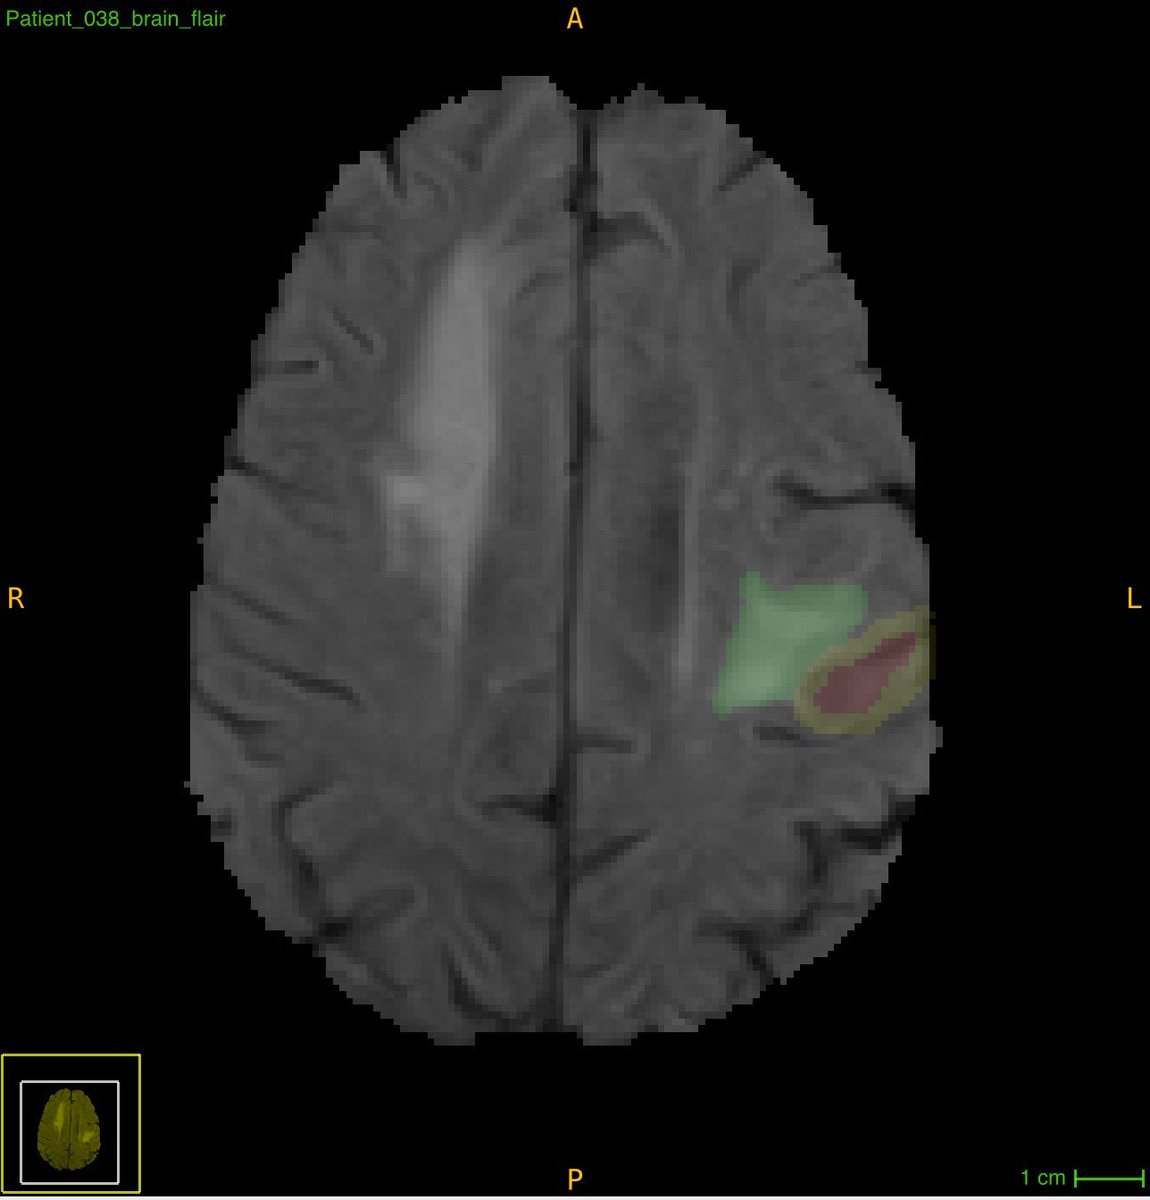

"Discover your passion & embrace it without overthinking" - one of the many inspiring lessons we learned today from @rad_Umber. #BraTS annotator team explored imaging informatics, focusing on improved patient care through better data management. Call us (junior) II experts! 🌟